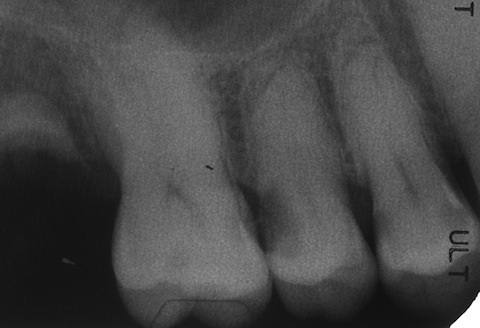

50代男性、右上5、6隣接面カリエス。冷水痛+。レントゲンで見ると、大きな虫歯に見えるが、肉眼ではそれほどでもない。エナメル質は全く溶けていないが、内部の象牙質だけが溶けている。この虫歯を見逃す歯医者はいないと思うが、なぜ象牙質だけが溶けるのか?という質問に答えられる歯医者は世界中探してもいない。できるのは僕だけwhttp://plaza.rakuten.co.jp/mabo400dc/diary/?PageId=11&ctgy=23歯はハイドロキシアパタイトというイオン電導性セラミックスが主成分で、電気(水素イオン)を通すことが知られていて、そのイオン化傾向を測ることもできる。http://plaza.rakuten.co.jp/mabo400dc/diary/201210150002/しかも象牙質の方がエナメル質よりわずかながらイオン化傾向が大きい。また、歯をpH3程度の酸性水溶液中に1ヶ月漬け込んでも溶けないが、外部から電圧をかけると簡単に溶ける。http://plaza.rakuten.co.jp/mabo400dc/diary/201210150000/これらのことから、この虫歯は象牙質とエナメル質を両電極とした局部電池が形成されることにより陰極となる象牙質だけが溶けると説明できる。ところが、世界中の歯医者はこのような虫歯を見慣れているが、なぜ、こういう虫歯ができるのかというのは知らない。ただ単に修復することができるだけだ。ところがCR充填すらできない歯医者は多い(というかほとんどだ)。なぜなら、世界中の歯医者は虫歯は細菌感染症だと思い込んでおり、虫歯を完全に除去しないと虫歯は再発すると信じ込んでいるからだ。このケースでは虫歯を完全に除去すると神経を取らざるを得なくなり、CR充填の適応症ではないと思い込んでいる。しかし、そうではない。虫歯を残しても、辺縁封鎖が完全なら、何の問題も生じない。要するに、虫歯があっても電気的に絶縁すればよいということだ。もちろん技術的な問題は大きいが。この症例のCR充填治療の所要時間は1時間。一回で終わり、神経も取らない、削って冠を被せるのも必要にならない。なんとコストパフォーマンスが高いことか!w